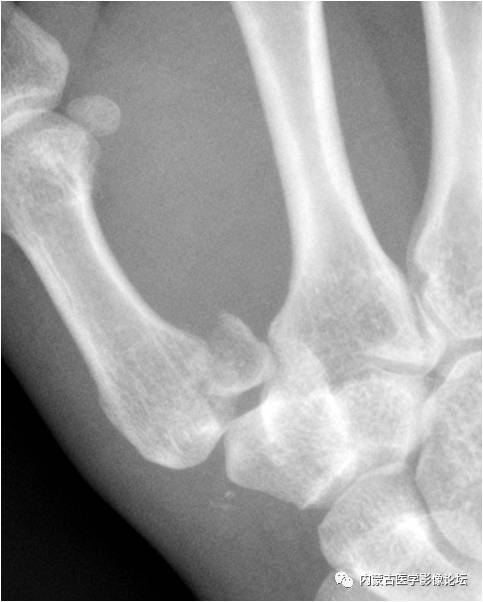

拇指籽骨:拇指指间关节籽骨(箭)较小且略呈三角形,与拇指掌指关节籽骨(箭头)不同,勿误认为撕脱骨折。